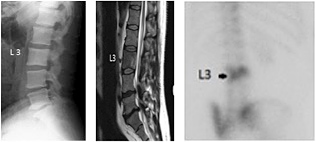

Do you notice the changes in the L3 vertebral body? (Fig.1) Even with my many years of reviewing spine films, I might have ignored the changes and focused on the clinical symptoms, leading me to just correlate the degenerative changes at the L5-S1 level.

Sagittal MR slice demonstrates the degenerative disc disease and disc herniation at the L4-5 and L5-S1 levels; and also indicates the L3 vertebral body is not normal. (Fig. 2) There are many reasons for changes demonstrated in the vertebral body: osteoblastic metastases, prostate cancer, lymphoma, Paget's disease, tuberculous spondylitis and hemangioma being the most probable differential diagnoses.

The patient's alkaline phosphatase level is 350 (reference range 40-125). Bone scan demonstrates increased uptakes at the L3 vertebra. Both of these findings are indicative of Paget's disease. (Fig. 3)

L3 vertebral body - Copyright – Stock Photo / Register Mark Clockwise from left: FIG 1 Lumbar spine; note changes in L3 vertebral body. FIG 2 Sagittal MRI lumbar T2 weighted image confirming changes at L3. FIG 3 Bone scan showing increased uptakes at L3 indicative of Paget's disease. Typically, patients with Paget's disease present with an isolated elevation in alkaline phosphatase level, but otherwise normal results of biochemical testing. In fact, the first indication of Paget's disease of bone is often an elevated serum alkaline phosphatase level or an abnormal radiograph in a patient whose health is being investigated for other reasons.1